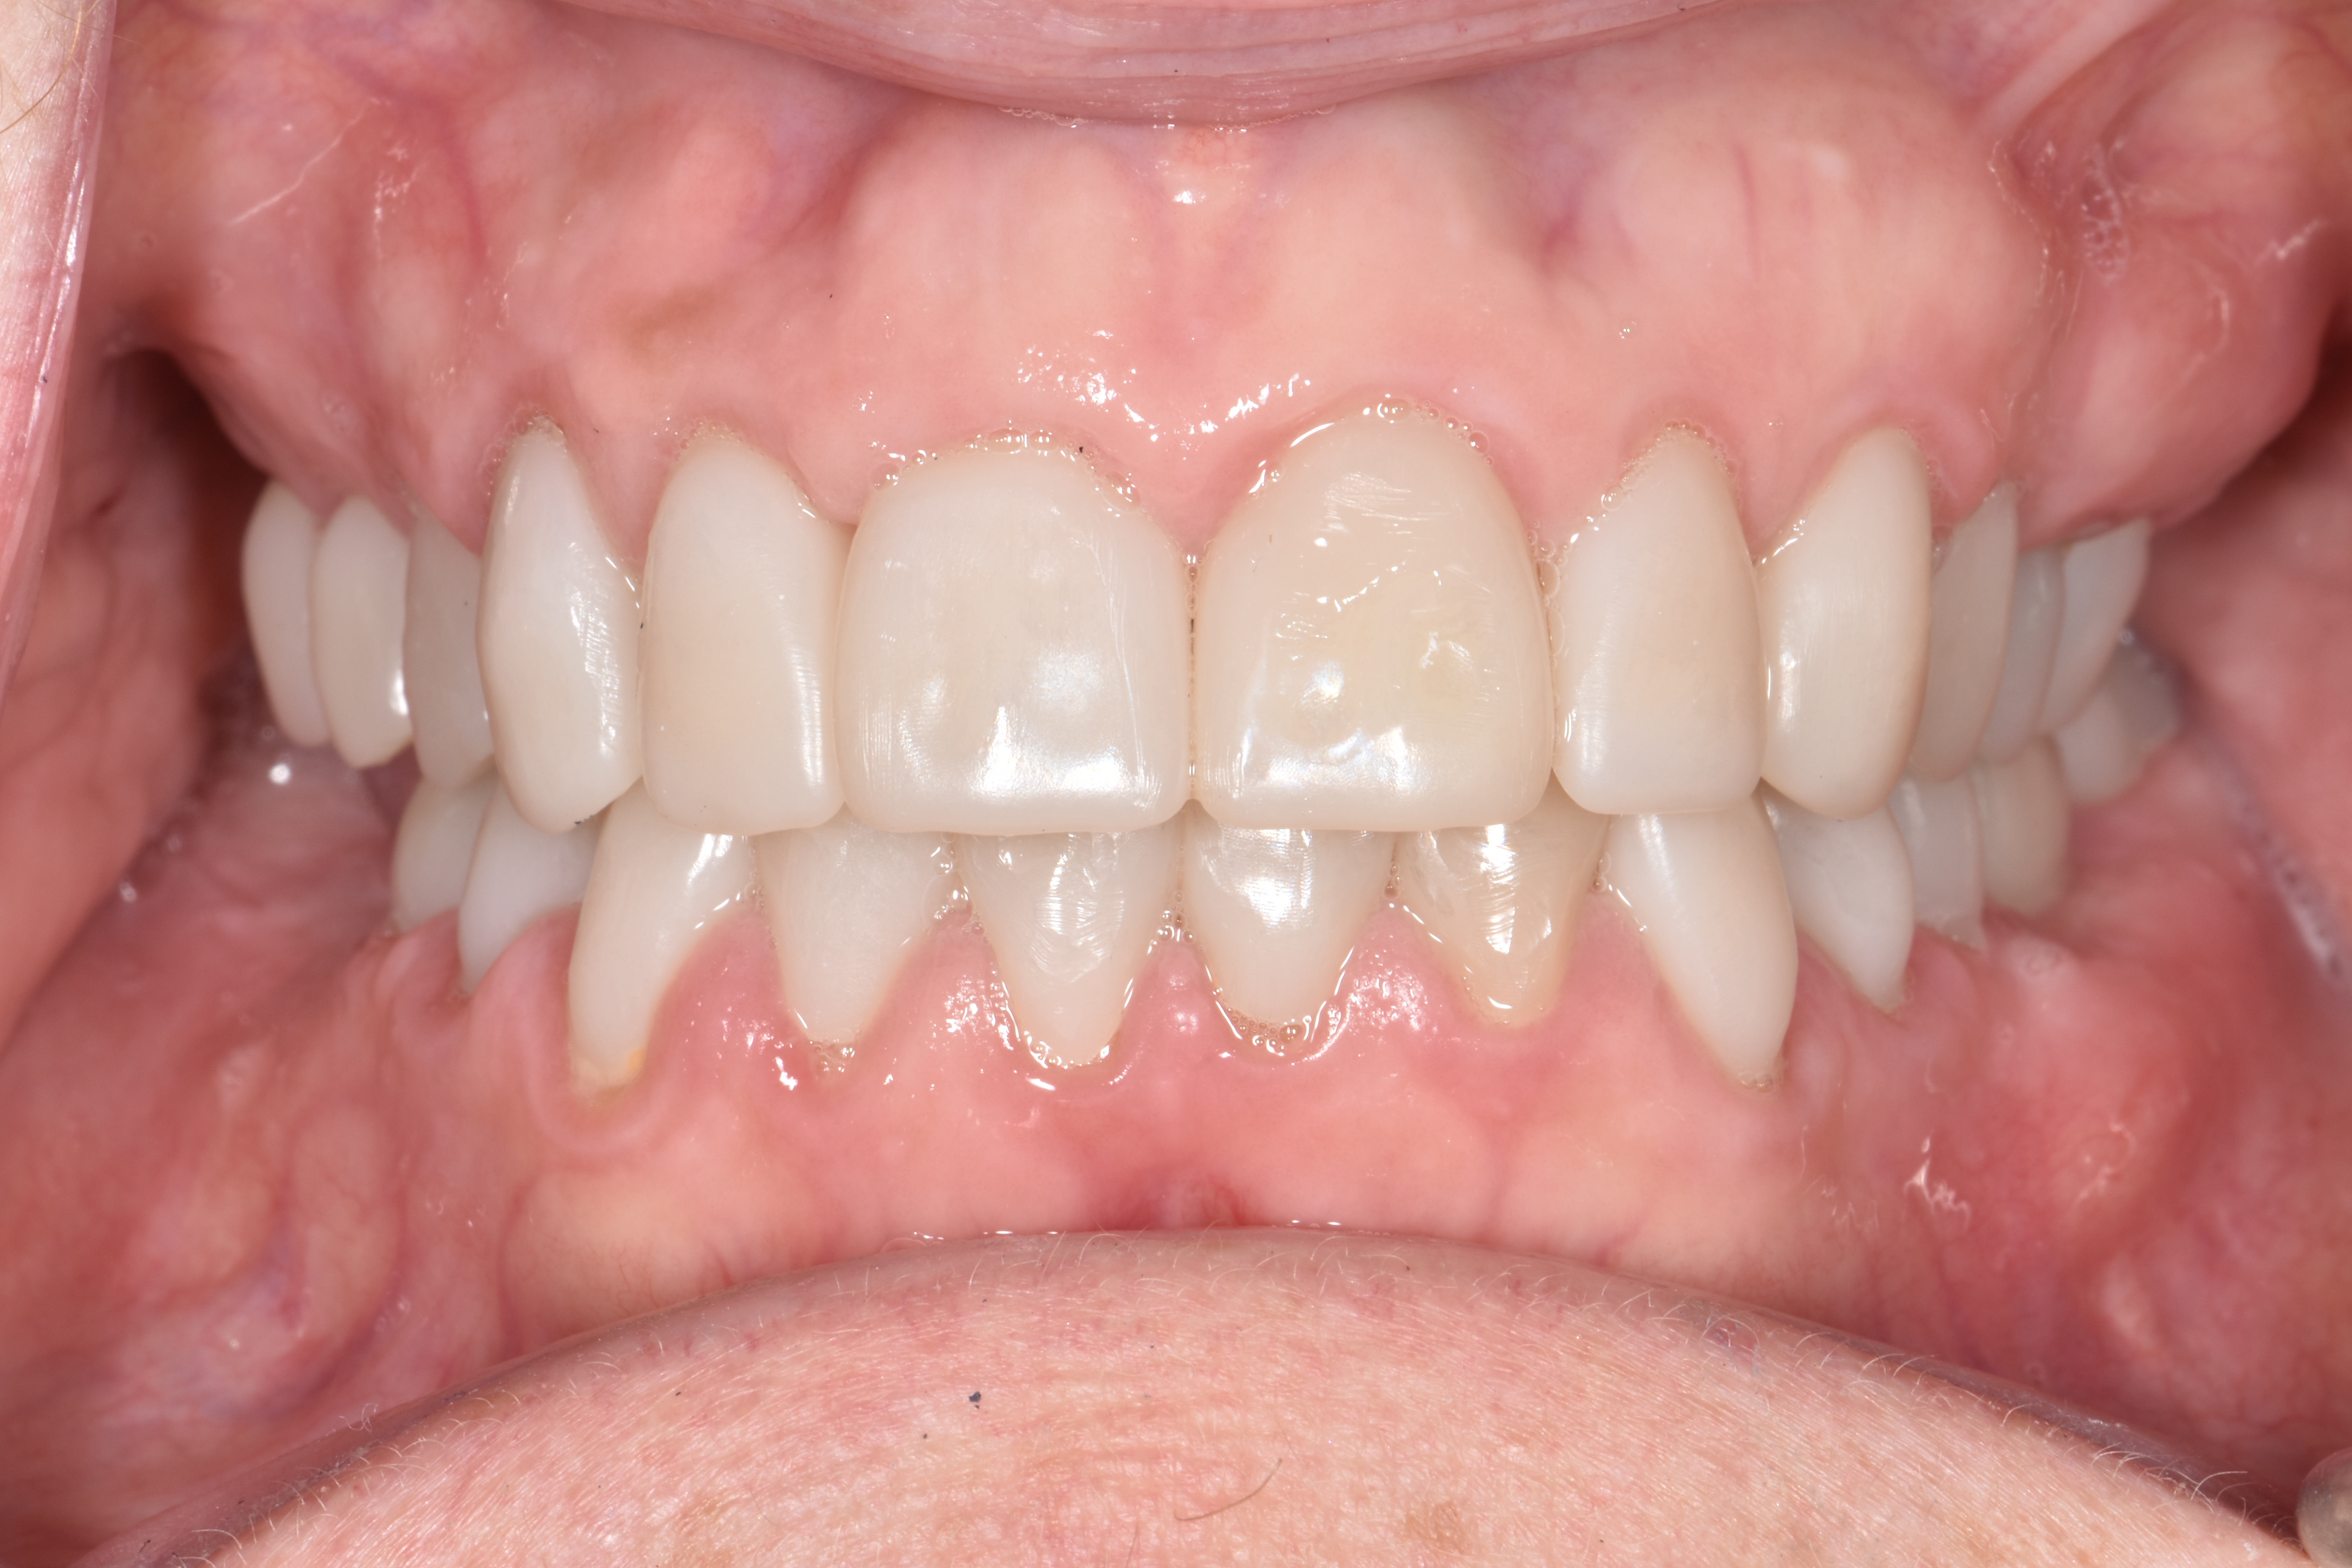

At a clinic treating patients in an underserved population, a 54-year-old female patient presented requesting extraction of all of her teeth and fabrication of dentures for her long-term restorations. The patient had a history of breast cancer, which had been treated with chemotherapy. She believed that full dentures would be an appropriate treatment option for her, owing to the poor state of her oral health and dentition and because she had limited financial resources and did not think that she could afford restoration of her teeth. The patient reported that she had experienced depression and alcohol abuse because of her cancer diagnosis, and that she had neglected her dental care during the course of her cancer treatment, resulting in generalized moderate-to-severe caries with moderate wear due to bruxism (Figure 1 through Figure 5). She also presented with significant staining of her remaining dentition due to the alcohol abuse.

After the restorations were milled, they were sintered and polished for final effect. It was decided that these restorations should not be glazed to avoid the added abrasivity that accompanies this finish to the restoration.22 The patient was then scheduled for temporary crown removal. The final crowns were fitted on the prepared teeth, and the contacts adjusted. The patient reported that she was pleased with the feel and esthetics of the restorations, and the restorations were cemented (Figure 14 through Figure 19).

Fig. 1

Fig. 2